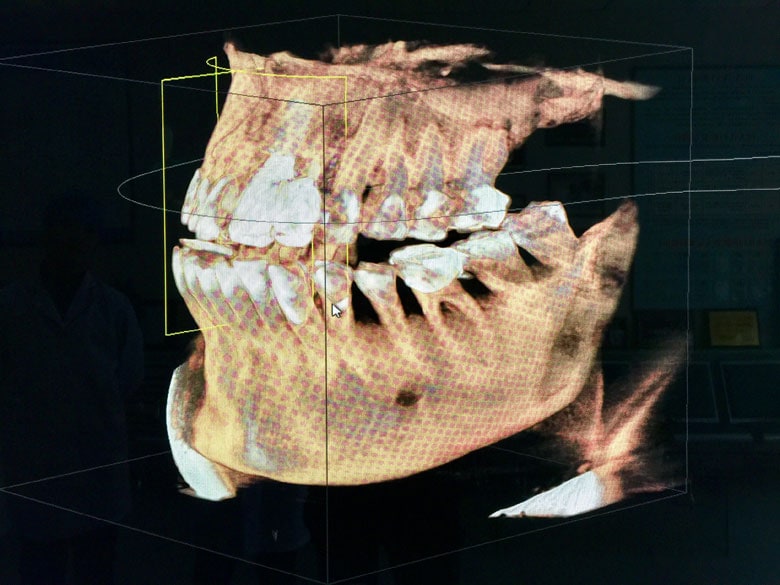

盤石市は中国の片田舎にある小さな町だ。そんな町の病院に期待は禁物だと思っていたが、いい意味で裏切られた。到着してみると、件の歯科医院は立派な建物で、中には最新鋭の機器がいっぱいだ。院長先生は最初に韓国で学び、その後はドイツ、アメリカで学んだ「海亀派」(留学帰国組を意味する中国語。帰国派と似た発音からつけられた掛け言葉)だという。